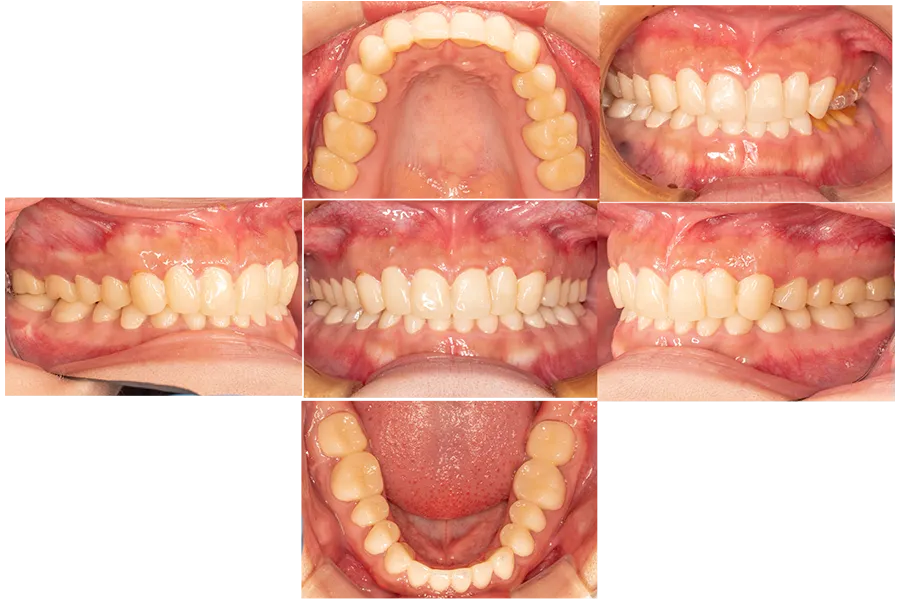

プロビジョナル

レストレーション

診断用ワックスアップをもとに、全顎プロビジョナルレストレーション(仮歯)を装着しました。

この期間に

- 咬合の安定

- 咀嚼機能

- 発音

- 審美性

を確認し、最終補綴の形態を決定します。

支台歯形成・精密印象

プロビジョナルで咬合が安定したことを確認後、全顎の支台歯形成を行い精密印象を採得しました。